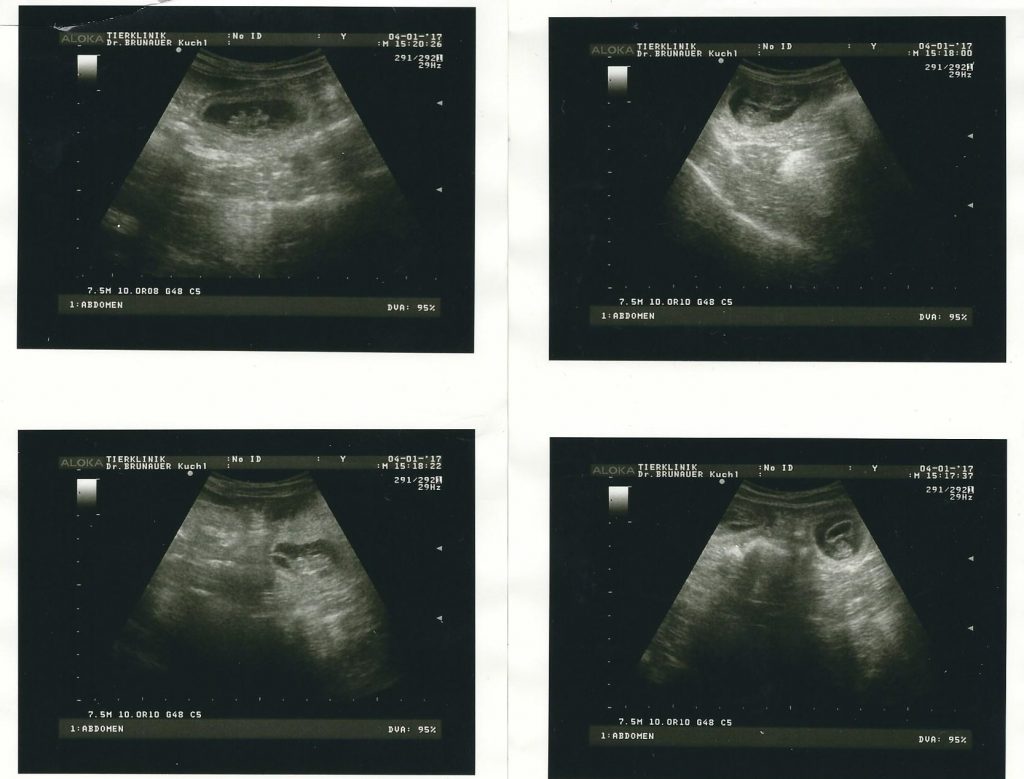

Am 4. Jänner 2017 Trächtigkeitsbestätigung mit Ultraschall,

haben 4 kleine Welpen-Föten gesehen.